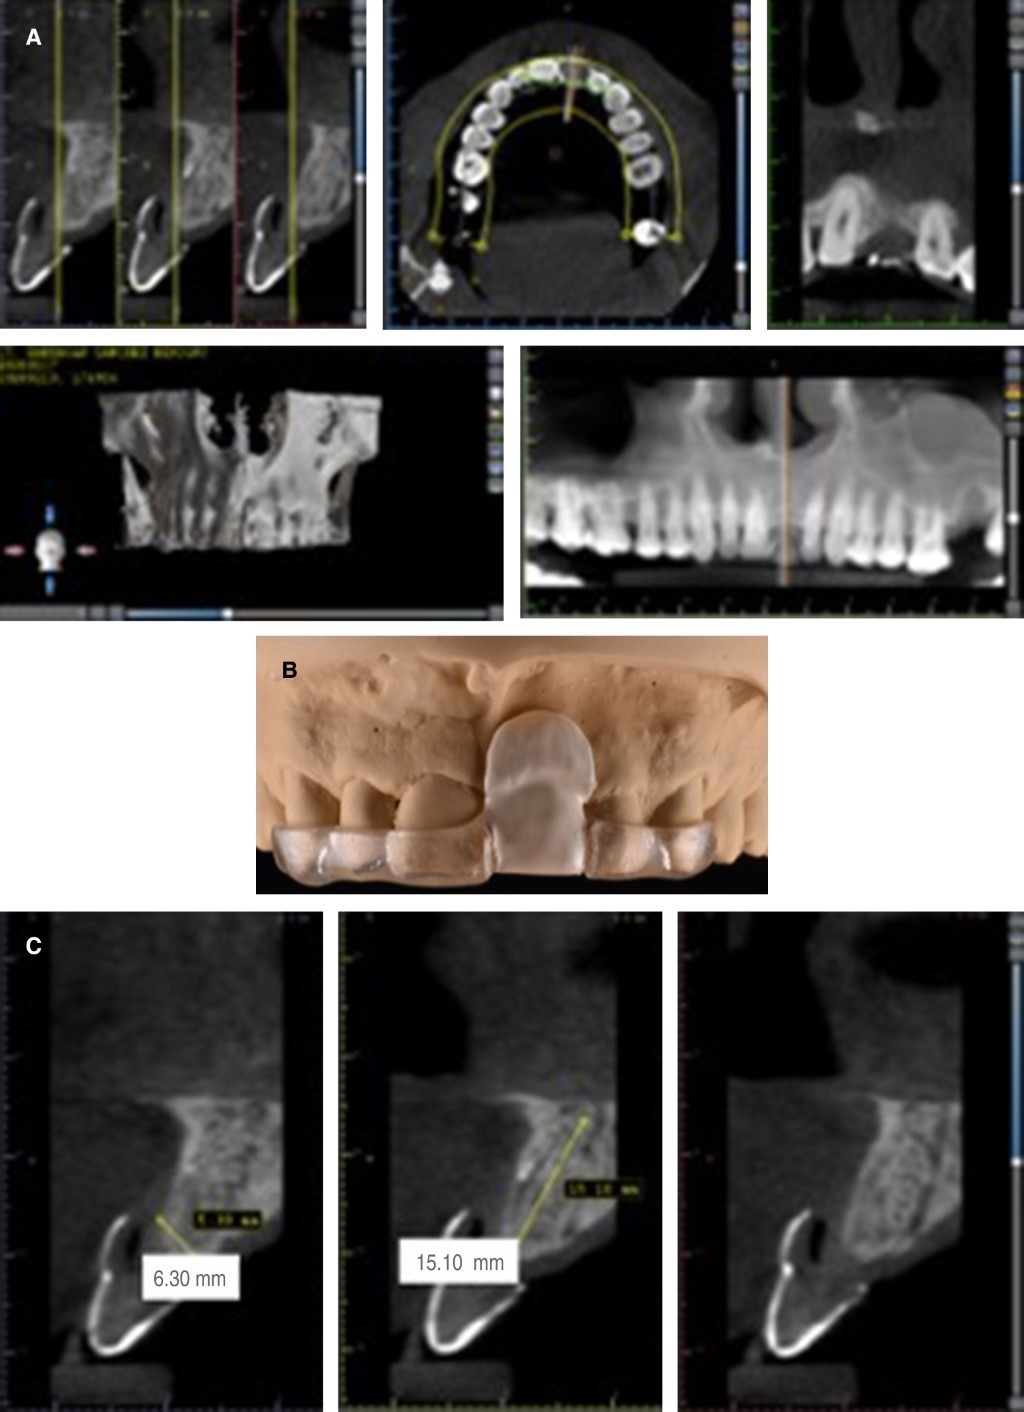

Periodontal and prosthetic phase I was performed, eliminating risk factors (caries, defective restorations, plaque, and calculus) and giving oral hygiene instructions. A cone beam computed tomography (CBCT) was indicated (Figure 5A) with the implementation of a tomographic guide elaborated from a diagnostic wax-up (Figure 5B) to observe the dimensions of the residual ridge (Figure 5C) and to choose an implant with ideal dimensions. Risk areas that may present a possible fenestration of the implant were identified to treat them adequately. Figure 6A shows the initial situation to be rehabilitated. Subsequently, we proceeded to the implant placement of tooth 21 (Straumann, SLActive, ø 3. 3, length 12 mm) using a restrictive guide (Figure 6B) for correct three-dimensional positioning in relation to the prosthetic dimension and the presence of bone tissue. The drilling sequence of the receptor site was started (Figure 6C-F) and the implant was inserted achieving primary stability of 35 Ncm2 (Figure 6G-I). Finally, the mesiodistal position of the implant was verified by taking a dentoalveolar radiograph (Figure 6J).

Figure 5